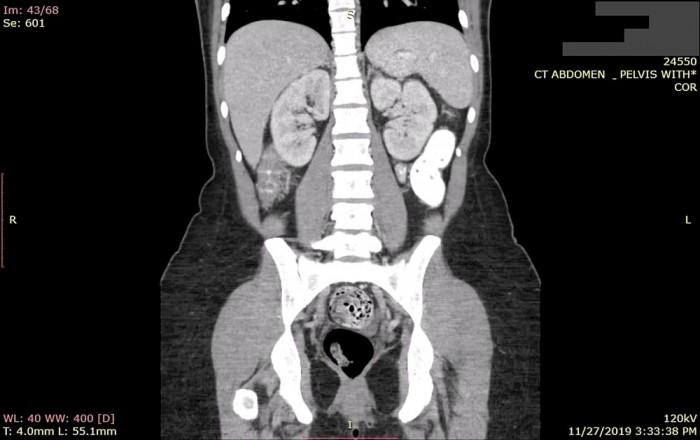

一项新的研究显示,美国绝大多数的医疗成像设备容易受到黑客攻击,一大原因是操作系统老旧,不受支持。根据Palo Alto Networks旗下Unit 42 Threat安全团队发布的《2020年物联网威胁报告》,多达83%的联网医疗成像设备(如乳房X光造影机、MRI核磁共振成像机等等)存在安全隐患。这一比例明显高于2018年的56%。

在报告中提到的一家未具名医院,一台乳腺X线机出现了异常流量。在短短几天的时间里,IT团队确定Conficker蠕虫感染了医院网络上的其他医疗设备,包括另一台乳腺X线机、一台放射机、一台数字成像设备以及其他的设备。